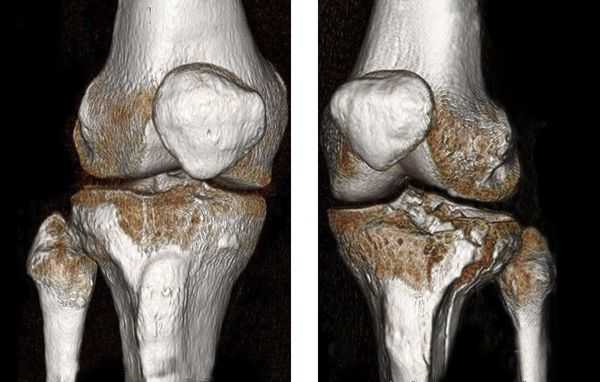

В некоторых случаях, если требуется детальная диагностика нескольких сегментов голени или пациент находится в тяжёлом состоянии, показана компьютерная томография с 3d-реконструкцией кости. Исследование можно проводить и при вынужденном положении конечности, но такой томограф есть не во всех клиниках. Поэтому в некоторых случаях, если информации недостаточно, делаются уточняющие прицельные рентгеновские снимки отдельных сегментов кости.

Хирургическое лечение состоит в открытой репозиции костных фрагментов и остеосинтезе — операции, при которой восстанавливают правильную ось ноги и придают отломкам нужное положение. Процедура проводится под общей анестезией. Подходящую технику остеосинтеза врач подбирает в зависимости от участка перелома.